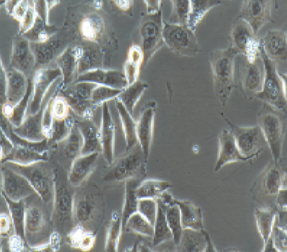

上皮细胞样,贴壁生长

2) 形态:上皮细胞样,贴壁生长

文献和实验我养的是膀胱癌 T24细胞(贴壁的)心得如下:1、 T24长的非常快,传代一般1:5传,每4天需要再传。2、虽然是永生化细胞,也一定不要等细胞100%汇合再传代,多次这样细胞状态不好,球形增加,还不容易洗掉。3、要用胰酶(0.25%)--EDTA(0.01%)混合消化液消化好些,一般1分钟内呈球形,即可混悬细胞了。4、培养液用10%小牛血清的DMEM或1640都可以。步骤:吸净培养液, PBS洗2次,加消化液室温一分钟左右,要在显微镜下注意观察,不要过头,球形后,吸掉消化液,加1毫升培养